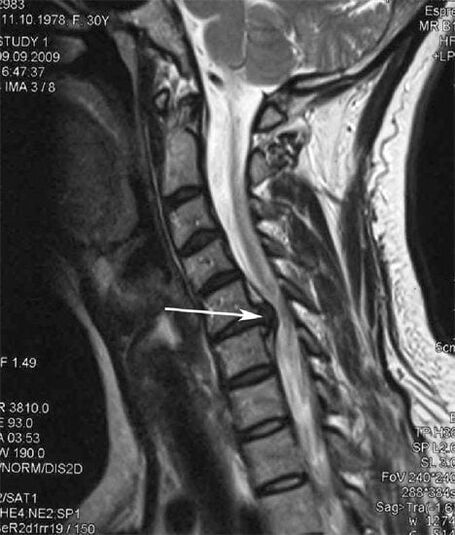

In the early stages, osteochondrosis is detected by MRI.Later, the pathology can be diagnosed using radiography.On x-rays of the cervical spine, a decrease in the distance between the vertebrae, pathological changes in the facet joints and osteophytosis become noticeable.

| Cervical osteochondrosis | The appearance of pathological changes in one or more motion segments of the spine.Impaired spinal mobility, development of myofascial pain syndromes and spinal root compression | Pain, paresthesia and motor disturbances in the cervical region, which spread to the back of the neck and upper limbs.Detection of characteristic changes in the spine on MRI and x-rays (osteophytes, decreased distance between vertebrae, signs of damage to intervertebral joints) |

Many people complain that they cannot turn their neck due to the severe pain that arises after lifting something heavy suddenly.This phenomenon indicates the formation of a herniated disc.The cause of pain in the back, neck and upper limbs is compression of one of the nerve roots that emerge from the spinal cord.